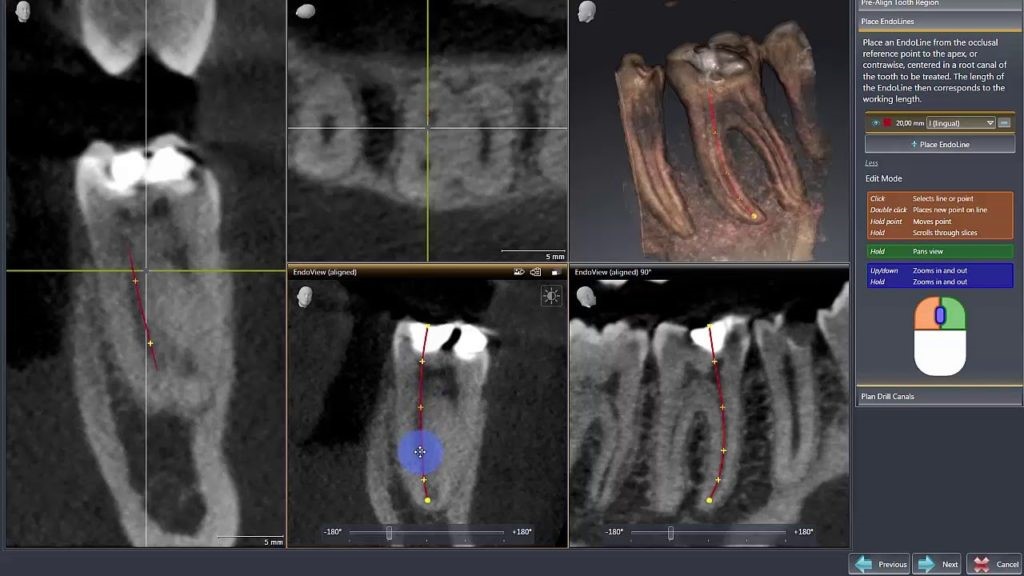

4. CBCT trong điều trị nội nha:

Trong điều trị tuỷ hay điều trị nội nha, cấu trúc giải phẫu ống tuỷ phức tạp như ống tuỷ chia sâu, ống tuỷ rẽ nhánh, các ống tuỷ phụ, ống tuỷ hình C và các tình trạng bệnh lý tuỷ như sỏi tuỷ, calci hoá ống tuỷ gây khó khăn rất nhiều cho việc điều trị và không thể thấy được trên phim X quang 2D thông thường.

Với phim chụp CBCT sẽ hỗ trợ tối đa cho Bác sĩ trong việc đánh giá giải phẫu ống tuỷ theo 3 chiều không gian cũng như phân tích được những cản trở, bệnh lý ống tuỷ hỗ trợ cho điều trị tốt hơn.

Phân tích ống tuỷ chân răng trên phim CBCT